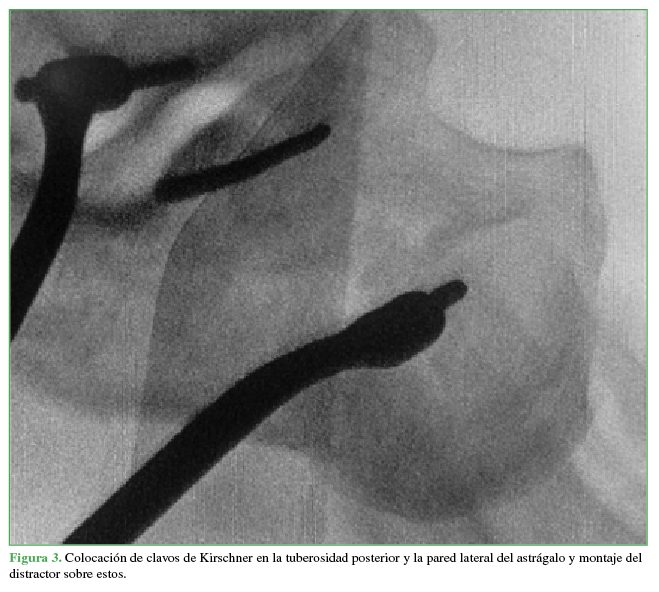

Se coloca un distractor con un clavo de Schanz de 5 mm esponjoso en la tuberosidad posterior y otro en la parte lateral del cuerpo del astrágalo si se pretende recuperar altura o en el cuboides para restaurar la longitud (Figura 3).